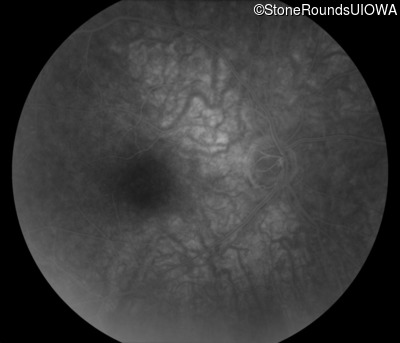

Infrared Fundus Photograph - Right - 20/20 -1

Exemplar